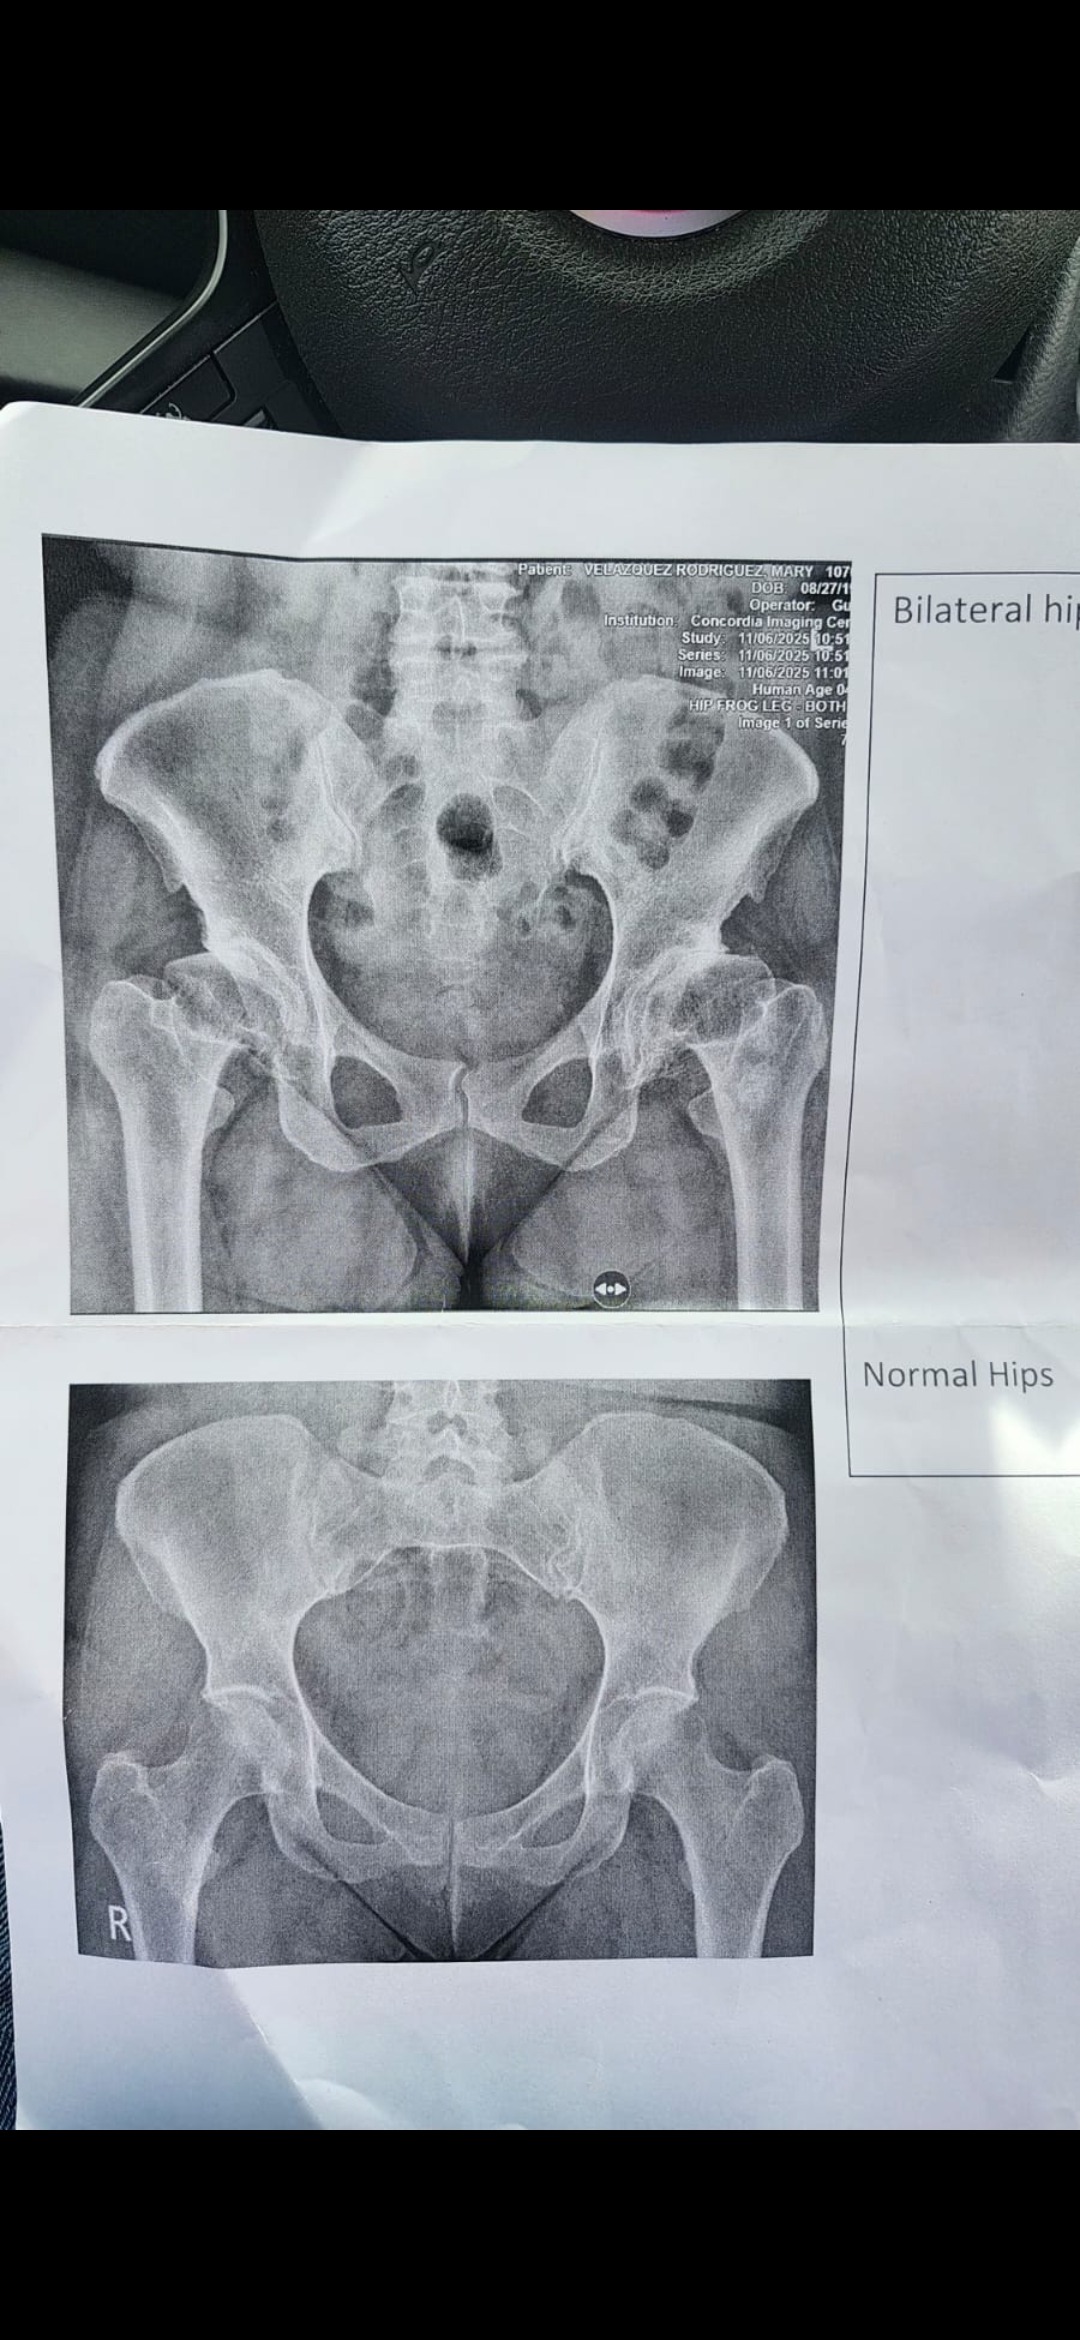

Bendecido, necesito de su ayuda para cubrir gastos médicos ( deducible que el plan médico no cubre); para remplazo de ambas caderas. Es importante para mí ya que no puedo caminar normalmente , soy una persona joven y deseo volver a tener una vida activa y normal.